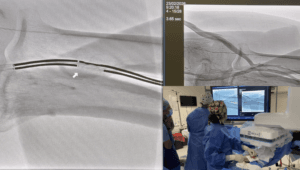

Embolización de varices pélvicas

El Dr. Andrés Guirola realiza embolización de varices pélvicas mediante cateterización de la vena gonadal.